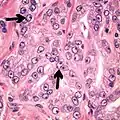

Ductal adenocarcinoma 3% to 12.7%[8][notes 1]

• Large glands and papillary formations, lined by tall columnar cells, often pseudostratified[1]

• Papillary, cribriform, individual glands, or solid variants[1]

• Cytoplasm usually amphophilic[1]

• Nuclei are large and hyperchromatic, with prominent nucleoli[9]

• AMACR+ in 77% of cases[1]

• Usually negative for basal cells stains[1]